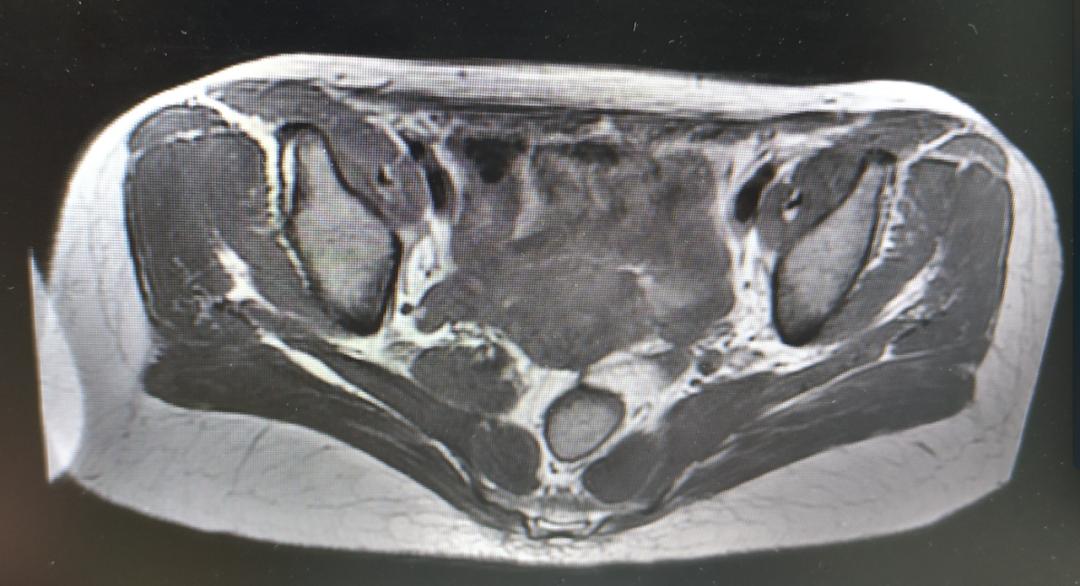

盆腔MR结果提示:

1、骶管、双侧骶椎间孔、骶骨及梨状肌前方盆腔内多发囊状信号影,考虑神经根袖囊肿,建议进一步检查;

2、右侧髋臼异常信号影,考虑血管瘤可能性大;

3、双侧腹股沟浅区小淋巴结显示。

神经外科会诊意见:患者查MR提示骶管、双侧骶椎间孔、骶骨及梨状肌前方盆腔内多发囊状信号影,考虑神经根袖囊肿。患者现无相关神经压迫等症状,建议定期复查,暂不考虑手术治疗。